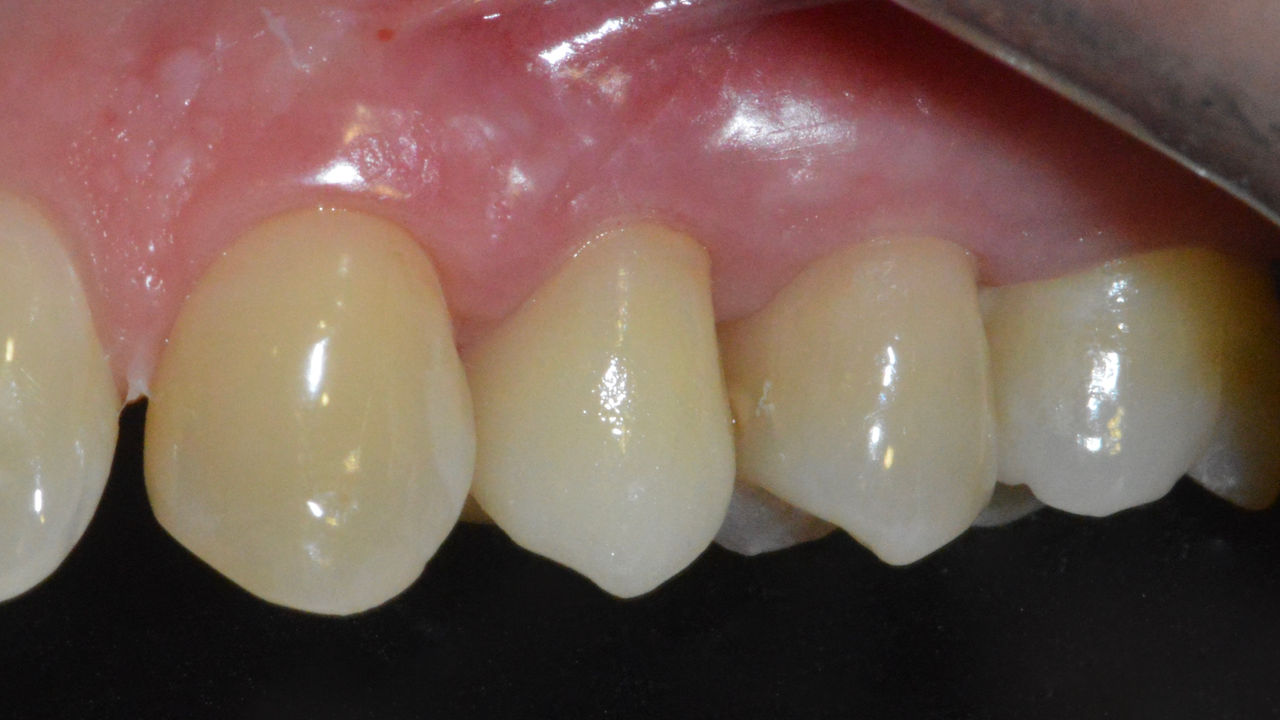

Antes: Obturaciones inadecuadas en los dientes 12 a 22, una línea gingival irregular en los dientes 12 y 11 y bordes incisales gravemente erosionados.

Después: Cuatro coronas de cerámica de disilicato de litio altamente estéticas e individualizadas.